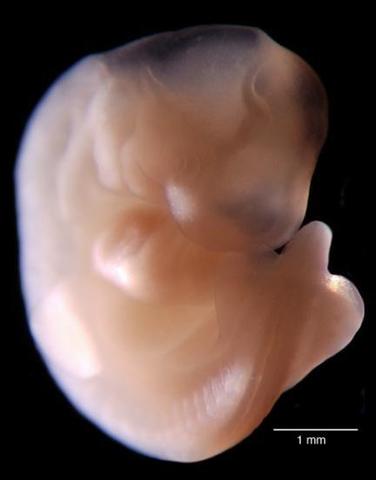

• 8va Semana de Gestación

8va Semana de Gestación

Termina el periodo de organogénesis, el crecimiento y maduración de todos los organos continuará en el periodo fetal

• Period: to

8va SDG

Externamente todas las estructuras están completas, la cabeza es mayor en relación con el tronco, las extremidades presentan sus 3 porciones , los dedos de manos y pies están separados aun que no tienen uñas el pédiculo de fijación se convierte en el cordón umbilical en el que todavía persiste la hernia fisiologíca la cual retornara a la cavidad abdominal en la decima semana , el embrión ya no presenta cola, el periodo embrionario termina en la 8va semana y empieza el periodo fetal.